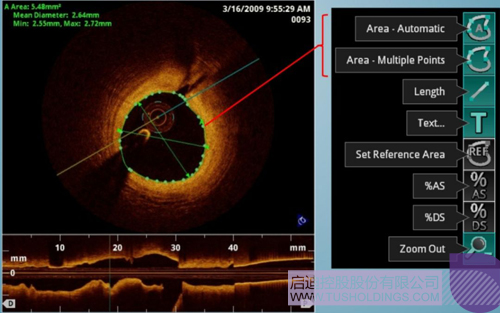

光学相干断层成像技术(OCT)是一种新型影像技术 ,它利用弱相干光干预仪的基来源理 ,检测生物组织差别深度层面对入射弱相干光的背向反射或频频散射信号 ,通过扫描 ,可获得生物组织二维或三维结构图像。OCT由于具有极高的区分率(10 um) ,可以对内膜性质和支架结构越发精确地区分和剖析。

在冠脉介入治疗迅猛生长的今天 ,随着庞大病变患者日益增多 ,血管内影像饰演了越来越重要的角色。OCT借助其高区分率的图像优势 ,可以提供更清晰的病变特征和支架植入情况 ,OCT保存以下优势:可更精确的检测介入治疗后的血管内情况 ,如夹层、支架贴壁不良、组织脱垂等 ,另外 ,它在管腔直径和面积方面的丈量精度更高。

血管腔内精准评估

中科微光接纳的是SS-OCT技术 ,该技术在临床上具备显著优势 ,例如回拉速度更快、采样帧数更多、宁静性更高。同时该技术也是目今OCT领域的最前沿技术 ,中科微光将争取实现海内首台内窥OCT造影系统商业化 ,资助医生在手术中凭据影像快速制定手术战略 ,资助患者有效减少急性心梗造成的死亡等。